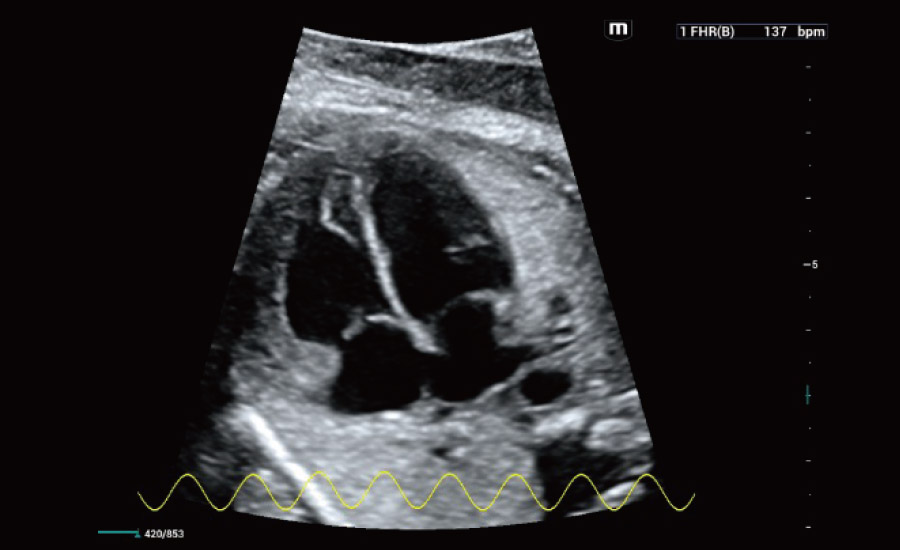

UMA (Ultra-Micro Angiography)

The innovative technology breaks the bottlenecks of traditional Doppler imaging. With ultra-high spatial resolution and flow sensitivity, it allows detecting super-subtle and super-slow flow perfusions, thereby extending the clinical application of qualitative and quantitative ultrasound evaluation in fetal brain, kidney, placenta, endometrium, ovary, etc.

Combining advanced algorithms and domain-specific knowledge, the innovative Smart Scene solution enables auto identification of tissue characteristics and provides organ-specific diagnosis with full-stack intelligence. Based on auto scenario identification, the solution not only realizes smart 2D scanning with auto settings and measurements, but also delivers 3D full-stack intelligence in every step from volume imaging optimization to the difficult 2D plane acquisition, and quantification throughout whole procedure. It helps a lot in reducing the dependency on clinical skills, while increasing diagnostic accuracy, confidence and efficiency.